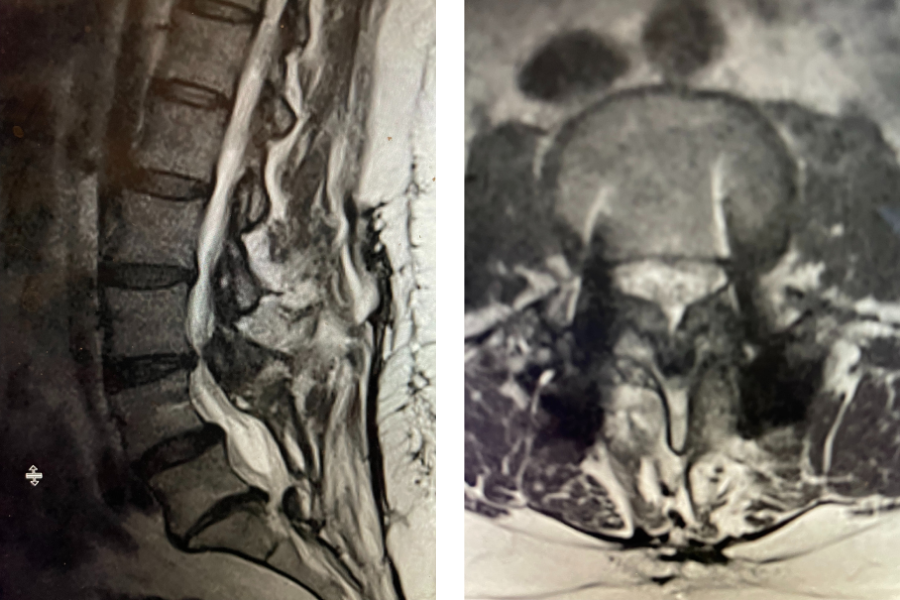

This 72 year old female had a long history of low back pain, leg pain, and scoliosis for which ten years ago she had a lumbar laminectomy followed by an instrumented L4-S1 fusion a year later. Since that time she had progressive low back pain and right lower extremity, weakness, and numbness. She presented with her leg symptoms being the biggest problem. MRI demonstrated a degenerative scoliosis with severe stenosis above the L4-S1 laminectomy and instrumented fusion. She had severe L2-3 and L3-4 stenosis. (Figs.3a,3b,3c 3d). After failing conservative management, she underwent an L2-L4 revision laminectomy and in situ fusion. She did well postoperatively. Considerations in performing a revision spine surgery is scar formation which initially makes it challenging to identify landmarks even in the region above that was not previously operated on. And of course during the dissection of compressive material on the dura, it is difficult to identify planes of separation and therefore an increased risk of a CSF leak. It was felt because of the severity of the scoliosis and her age we augmented the laminectomy with an in situ fusion, or a fusion with just bone graft without instrumentation. It is controversial whether a fusion is actually necessary in the case of a stable degenerative scoliosis with stenosis but the accepted approach is to perform a fusion If an instrumented fusion is considered it would require at least a T11-pelvis fusion. Since we performed only a 2 level laminectomy with a severely osteophytic spine, we compromised with an in situ fusion, reducing blood loss, operating time, and risk for infection. Because of the degree of spondylotic disease as a result of the stresses and strains on the spine given the scoliosis, the spine attempts to auto stabilize by forming these buttresses of arthritic material.

Fig 3a: Coronal T2-weighted MRI demonstrating significant detro lumbar degenerative scoliosis with a prior L4-S1 instrumented fusion. Note lateral listhesis of the L3-4; Figs 3b and 3c: Sagittal and axial T2- weighted MRIs showing severe lumbar stenosis above the prior L4-S1 fusion; Fig 3d showing an axial image T2-weighted MRI at the level of the prior L4-5 portion of the fusion showing no recurrent stenosis